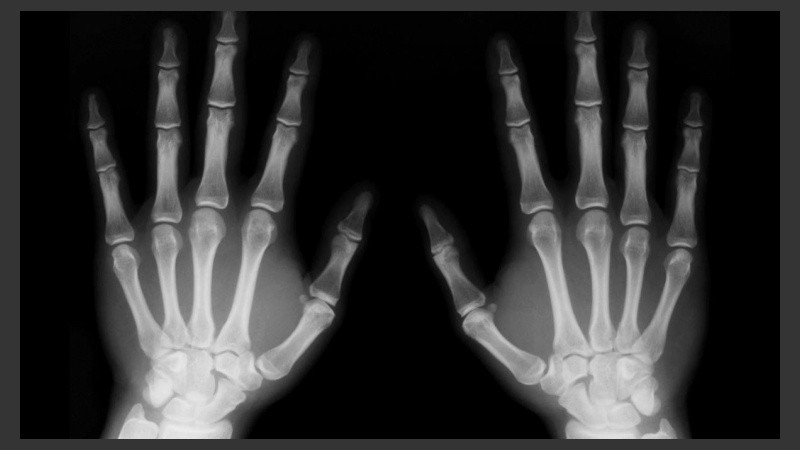

El viernes 7 de agosto, en el Auditorio del Cemar (San Luis 2020), se concretó un encuentro de capacitación orientado a trabajadores del área expuestos a radiaciones y al manejo de residuos peligrosos, a cargo de la Superintendencia de Riesgos del Trabajo de la Nación (SRT). Además, desde el organismo nacional inspeccionaron distintas dependencias del área de Salud y destacaron el avance en las gestiones del municipio para minimizar los efectos adversos que produce la utilización de Rayos X en profesionales y el medio ambiente.

Durante el encuentro, organizado en conjunto con la Municipalidad de Rosario, la Dirección de Diagnóstico por Imágenes de la Secretaría de Salud Pública, el Sindicato de Trabajadores Municipales y el Colegio Profesional de Técnicos Radiólogos, se remarcó que existen profesionales de diferentes especialidades de la salud que utilizan Rayos X sin conocer los efectos adversos de los mismos, por lo que es fundamental capacitar a los trabajadores para cuidar a los pacientes y a los propios empleados.

Cabe destacar que la Secretaría de Salud Pública está incorporando aparatos de diagnóstico por imágenes calibrados para ser utilizados con protocolos de radioprotección, tendientes a resguardar a pacientes, adultos y pediátricos y lograr de esta manera la mejor imagen con la menor radiación posible.